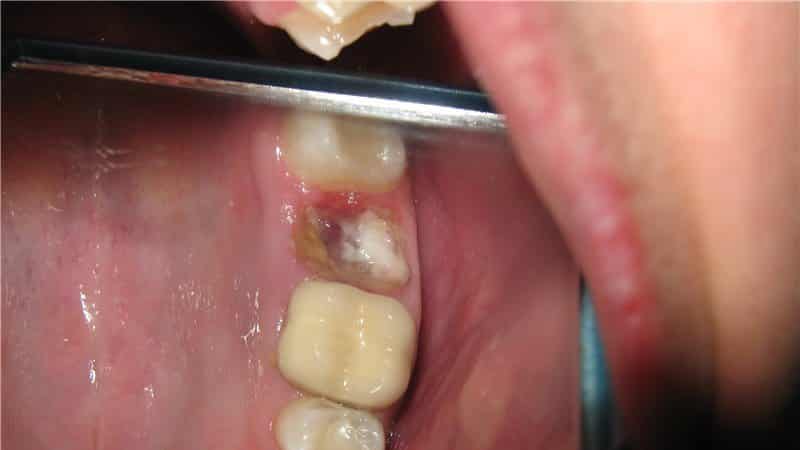

Коренные зубы обычно удаляются в случае серьезного повреждения кариесом и невозможности их восстановления лечением. Также полностью удаляются зубы с переломом корня. Перед удалением проводится рентген, чтобы определить точное расположение корня. Сейчас процедура выполняется с использованием обезболивающих инъекций. Хирург-стоматолог захватывает зуб щипцами, раскачивает его и выдергивает, предварительно разделяя коронку зуба на части, чтобы предотвратить травмирование челюсти. Удаление коренного зуба может быть болезненным и сложным в случае хрупкой структуры коронки, искривленных корней, разрушения под корень, неполного прорезывания или наличия кисты. После удаления зуба необходимо сделать рентген, чтобы проверить, нет ли остатков корневых частичек. В некоторых сложных случаях может потребоваться разрезание слизистой и общий наркоз.

Удаление коренного зуба является сложной процедурой, и стоматолог принимает решение на основе обследования и рентгеновского снимка, которые содержат следующие рекомендации:

- Наличие опухолей или кистозных образований.

- Гнойно-воспалительные процессы, вызванные периодонтитом.

- Образование абсцесса, флегмона или гнойного периостита.

- Обнаженная пульпа или перелом по оси коронки.

- Разрушенная коронка.